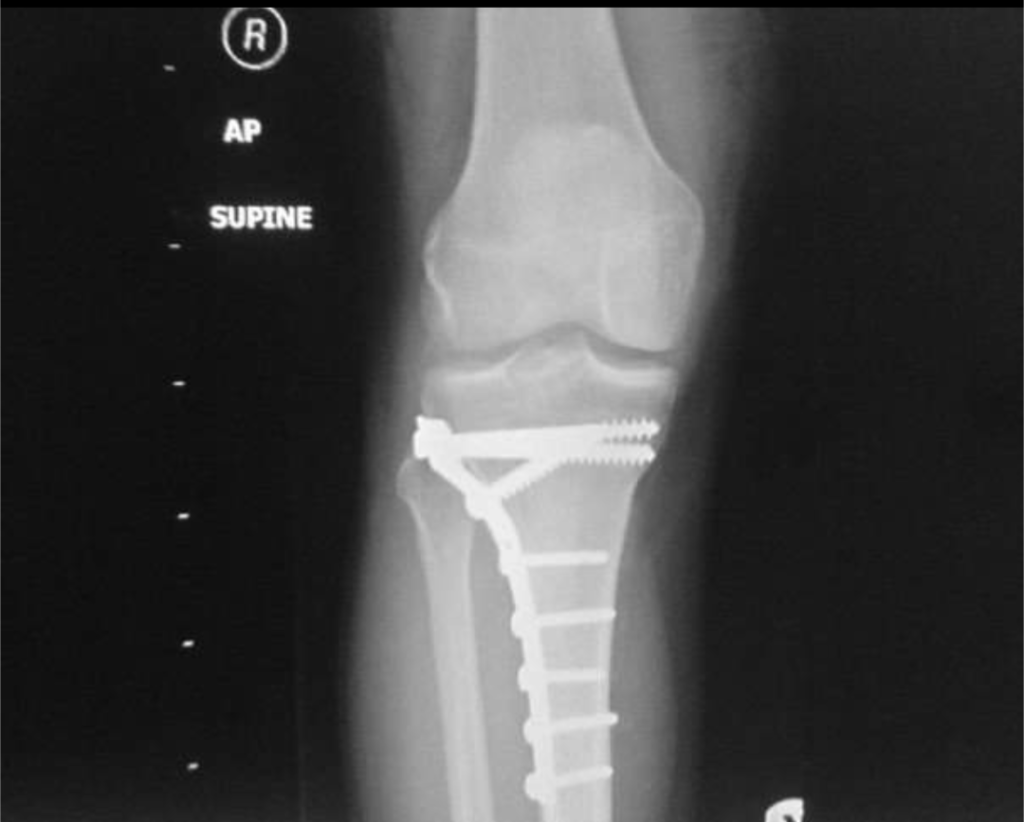

Turned out I'd broken my tibial plateau.

CT scan